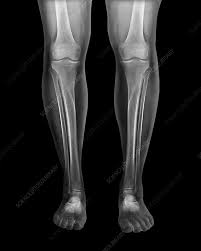

– X-ray

X-ray is an imaging test which is done to identify issues related to bone or fractures.